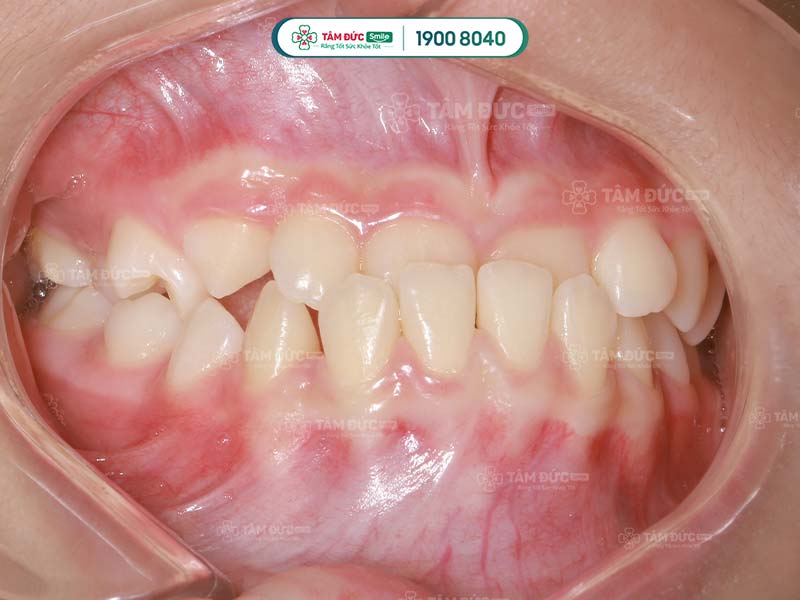

Xương hàm dưới đưa ra hay còn gọi là khớp cắn ngược, hình thành do sai lệch về cấu trúc xương hàm và mặt. Điều này làm xương hàm dưới nhô ra xa hơn so với xương hàm trên.

Biểu hiện của bệnh lý này rõ nhất khi Quý khách ngậm miệng, phần răng ở hàm dưới sẽ không khớp với hàm trên. Trong một số trường hợp, xương hàm dưới còn bao phủ luôn hàm trên.

Dựa vào khả năng bao phủ của hàm dưới, các bác sĩ sẽ đánh giá tình trạng xương hàm dưới đưa ra của Quý khách là nặng hay nhẹ.

- Xương hàm dưới đưa ra do răng: Trường hợp này xảy ra do răng ở hàm dưới mọc xiên về phía trước tạo nên khớp cắn ngược.

- Xương hàm dưới đưa ra do hàm: Phần xương hàm dưới phát triển quá mức làm mất cân bằng cấu trúc hàm.

- Xương hàm dưới đưa ra do cả xương hàm và răng: Đây là trường hợp hiếm gặp, cả xương hàm và răng phát triển sai lệch làm cho xương hàm dưới đưa ra.